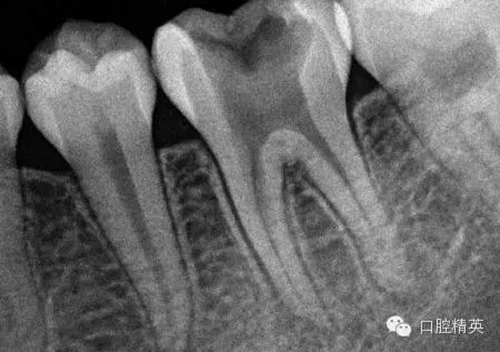

1,術(shù)前X-ray,常規(guī)術(shù)前攝片,為患者和自己保留一份客觀記錄。

3,術(shù)前左下6近中根管斷針X-P,斷針長度約4MM,根尖慢性炎癥影像。。。

9,斷針取出術(shù)后X-P,RCT待續(xù)。。。